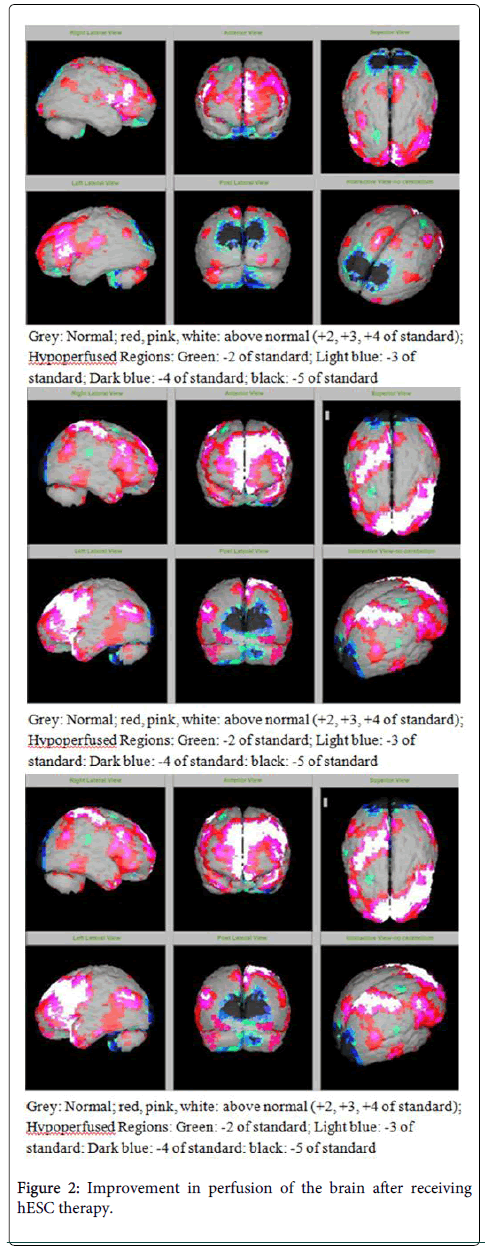

該患者的SPECT掃描如圖1和2所示。

SPECT掃描

在研究開始和結(jié)束時,23名患者接受了SPECT掃描。在枕葉或額葉或雙葉中觀察到灌注不足。23例接受SPECT掃描的患者中,5例患者表現(xiàn)為枕葉灌注不足,7例患者表現(xiàn)為額葉灌注不足,11例患者表現(xiàn)為枕葉和額葉灌注不足。

總體而言,治療結(jié)束時,2名患者的灌注正常,18名患者(12名男性和6名女性患者)顯示灌注顯著改善(>60%),3名患者顯示灌注中度改善(30-60%)。大多數(shù)在接受hESC治療前額葉和枕葉嚴重低灌注的患者在接受 hESC 治療后情況有所改善。23名可獲得SPECT掃描報告的患者的GMFCS評分在hESC治療后有所改善(表2)。

眾所周知,神經(jīng)干細胞可以通過重新填充受損區(qū)域并防止細胞進一步退化來恢復正常視力。hESC通過增殖成相似的細胞類型來啟動受損細胞的再生。在本研究中觀察到灌注改善,這反映在SPECT掃描中。詹森等人研究顯示,一名5歲腦癱患者在接受臍帶血干細胞治療2個月后視力有所改善。